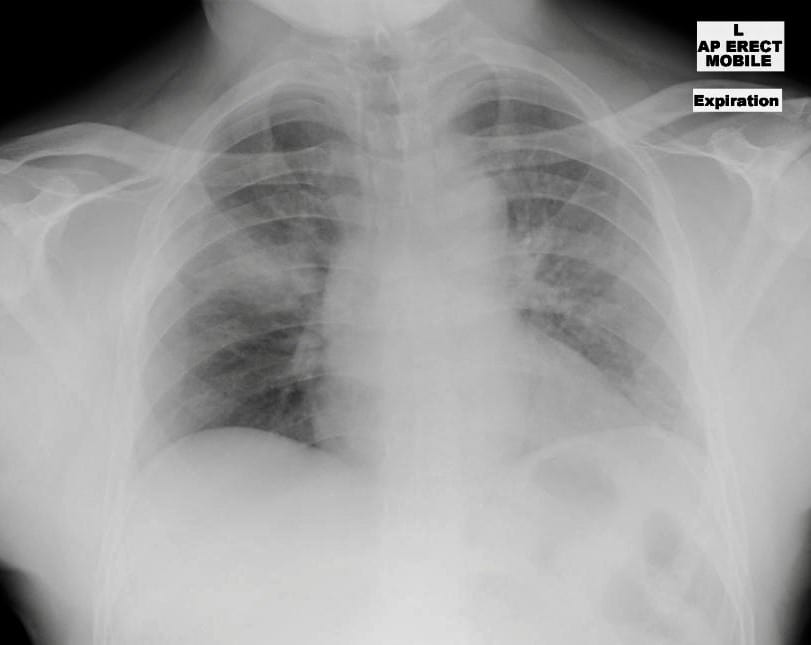

From buyxraysonline.com

TRAUMA CHEST Small Stabs In Chest Sudden, sharp chest pain lasts for less than a few seconds. Chest pain is the most common symptom of pericarditis. An injury such as broken or bruised ribs. The telltale symptom of precordial catch syndrome is a sharp pain in the left side of your chest near your heart. You may be able to. If you have sudden, sharp, momentary. Small Stabs In Chest.